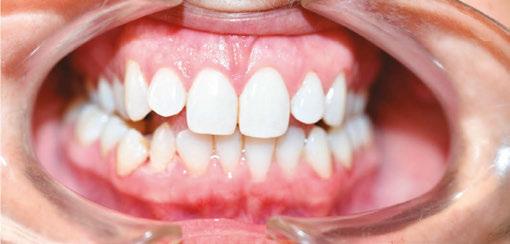

Patient J, a 39-year-old female, (Figures 1, 2, 3, 4, 5, 6) came to the office with concerns about difficulties chewing food and experiencing dry mouth upon waking up in the morning. Additionally, her partner was disturbed by her snoring. Upon examination, several issues came to light:

1. An open bite in the anterior region and a posterior crossbite

2. Breathing through the nose 10% of the time.

3. Lips and cheek muscles actively helping with swallowing food and drinks

4. Lips open 100% of the time

5. Tongue cannot maintain position on a spot, moves between teeth upon swallowing

6. Tongue thrust

7. Weak control over soft palate

Muscle tension around the temporomandibular joint (TMJ) was also evident5 as well as mandibular bilateral lingual torus as response to constant occlusal pressure applied during bruxism.

Figure 2: Anterior view before treatment